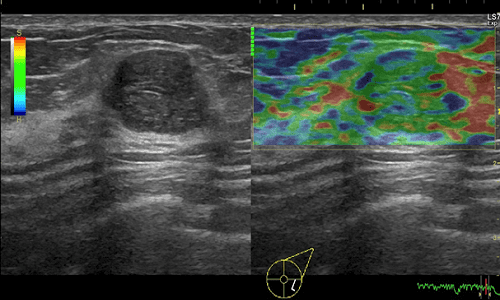

Mô tả sơ bộ: Siêu âm đàn hồi mô là một kỹ thuật siêu âm đánh giá độ cứng của mô thông qua mức độ đàn hồi của mô khi chịu tác động của lực cơ học. Các mô bệnh lý có thể có cùng độ phản hồi âm, nhưng chúng có độ cứng khác nhau, các mô càng ác tính thì độ cứng càng tăng. Vì vậy khi đánh giá được độ cứng của mô tổn thương sẽ cung cấp thêm thông tin về bản chất của mô đó. Những mô bệnh lý có cùng độ phản hồi âm thì trên hình ảnh siêu âm B mode khó phân biệt tính chất lành tính hay ác tính, siêu âm Dopplercó thể hỗ trợ thêm cho nhận định, những khối u ác thường tăng sinh mạch máu nhiều, nhưng nhiều trường hợp sự tăng sinh mạch máu cũng không rõ ràng vì vậy vẫn khó nhận định tính chất lành tính hay ác tính. Siêu âm đàn hồi mô sẽ giúp bổ xung thêm thông tin về đặc tính của mô tổn thương để làm tăng khả năng chẩn đoán. Siêu âm đàn hồi mô luôn được làm cùng siêu âm B – mode, không bao giờ làm siêu âm đàn hồi mô đơn độc.

Đầu dò siêu âm sẽ thu nhận sóng này và mã hóa ra bằng màu sắc để tạo ra bản đồ đàn hồi mô, từ đó giúp ta lượng hóa được độ cứng của mô, đơn vị là m/s hoặc kPa.

- Độ cứng tương đối của tổn thương (Elasticity score – ES). Độ cứng được xác định bằng màu sắc tương ứng với thang màu quy ước, thường được chia ra làm 4 hoặc 5 score. Score 1 là mềm, score 2 và 3 là trung gian, score 4 là cứng.

Phân loại elastogram score (ES) về độ cứng của mô tổn thương theo Flob và cộng sự: số thứ tự từ score 1 đến score 5 từ trên xuống dưới.